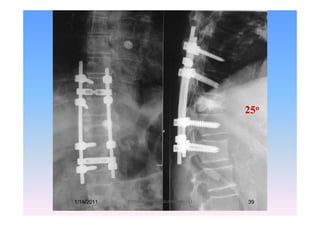

73-year-old man with T11 Lesion ( Prostate Ca.)1/14/2011 38Professor Freih AbuHassan -UJ

25o25

1/14/2011 39Professor Freih AbuHassan -UJ